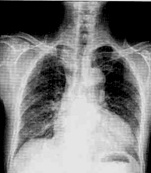

病史:女性,76岁,胸闷伴呼吸困难6天,不能平卧1天。诊断:

○右侧胸腔积液

○右下肺不张

○右下胸膜肥厚

○大叶肺炎

○气胸